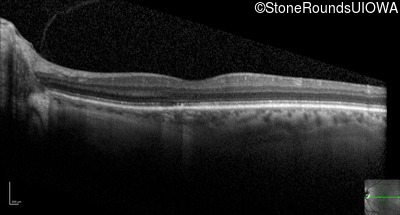

Optical Coherence Tomography - Right - 20/100

Exemplar / OCT Stack

OCT Stack